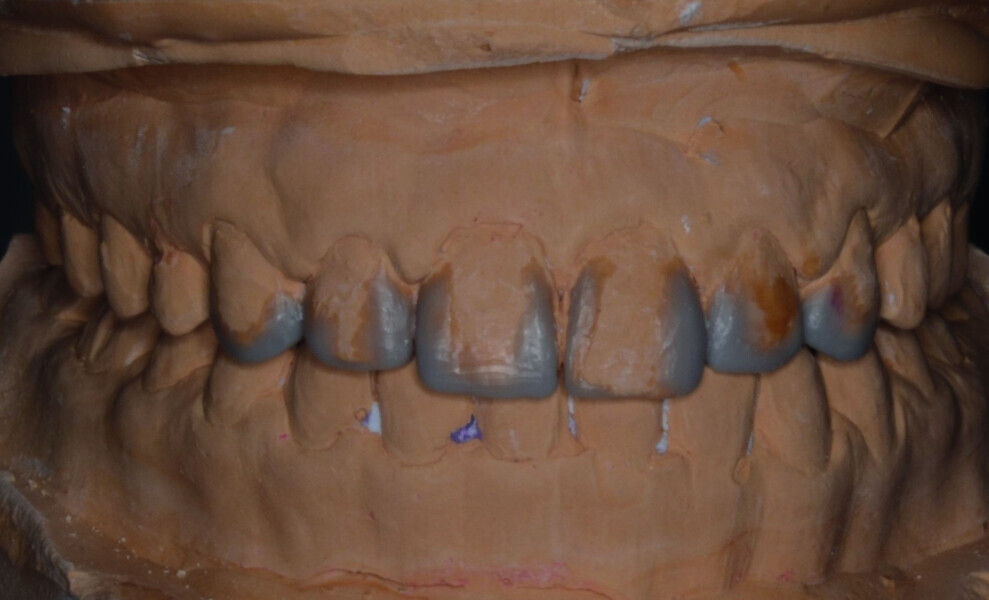

Orthodontic management of maxillary lateral incisors agenesis